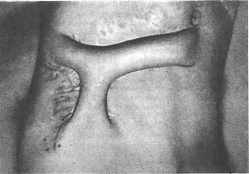

Филатовский стебель на двух питающих ножках.

Формирование стебля по методу Филатова